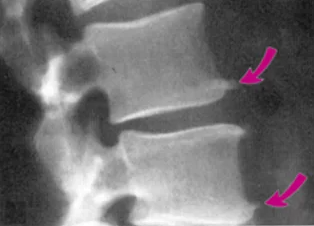

🦴 2. 腰椎骨刺(腰椎退化性關節病)

📍常見族群: 久坐族、重體力工作者、運動員、中壯年族群。

📍症狀表現:

- 下背僵硬、久坐後起身困難

- 腰痠、放射到臀部與腿部(坐骨神經痛樣)

- 彎腰、起床、走路時都會痛

- 嚴重時甚至走幾步路就得停下來休息

👉 骨刺若壓迫到脊椎神經根,就可能出現典型的「下肢放射痛」。